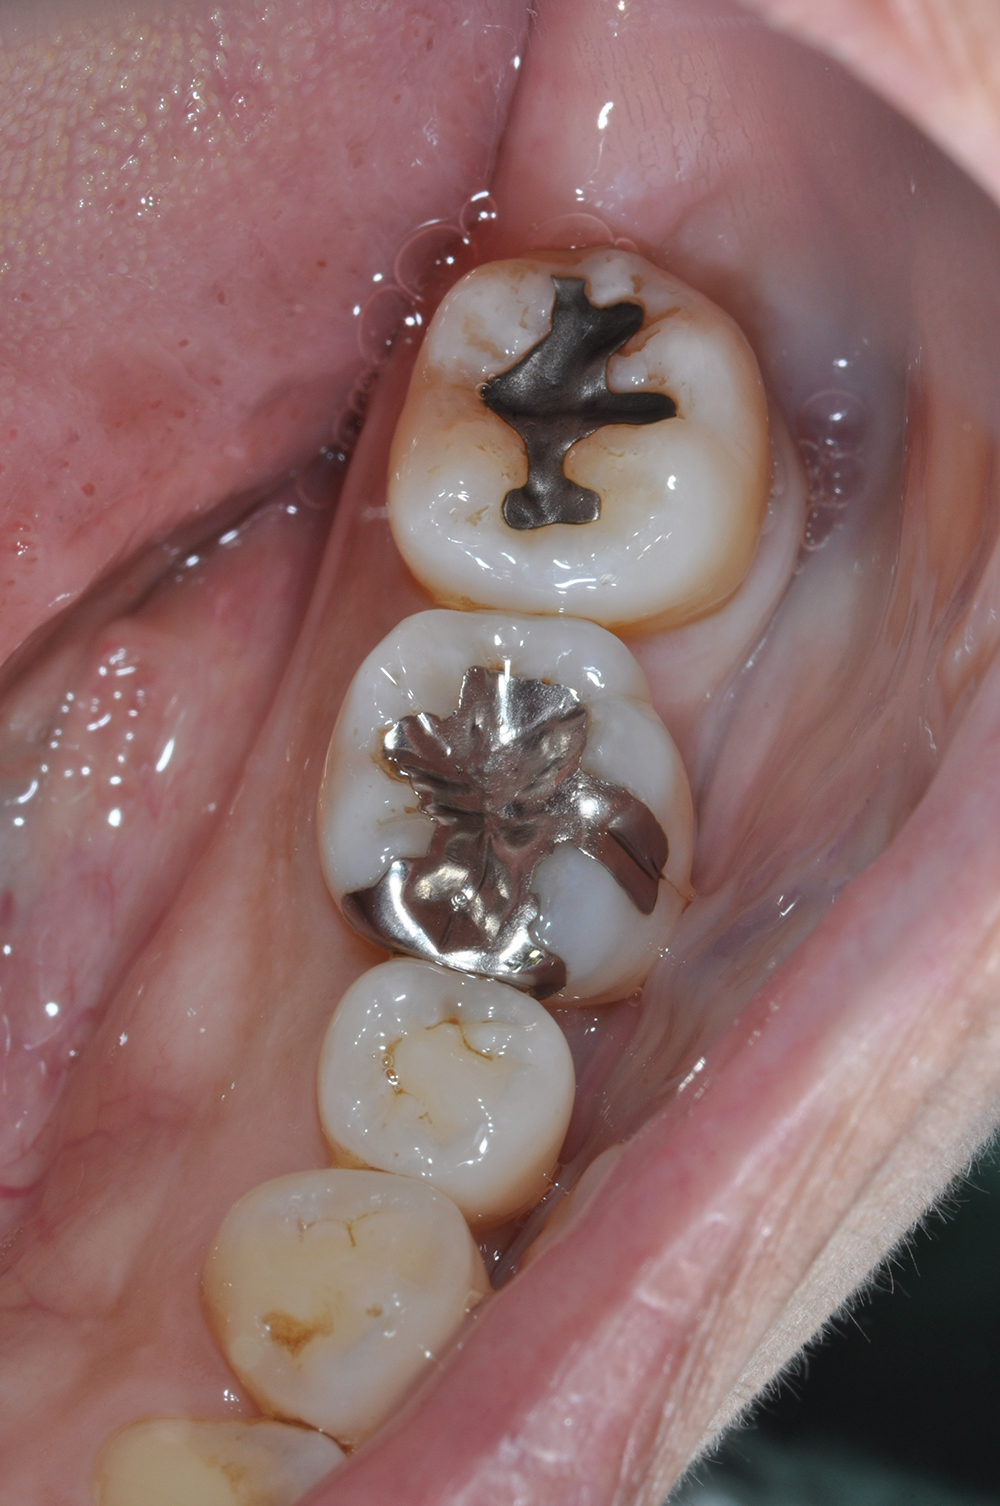

術前

術後

世代・性別

40代女性

主訴

ずっと痛い、噛むと特に痛い、前医でもうこれ以上はできないと言われた

治療内容

根管治療

治療期間

2ヶ月

治療費

保険適応内

治療のリスク

治療中または治療後に、一時的な痛みや腫れが生じることがある